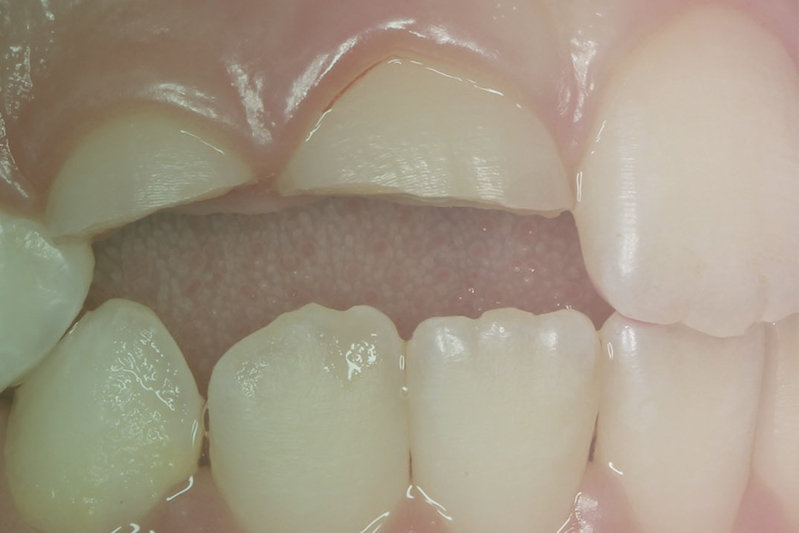

Клинический случай. Эндодонтия